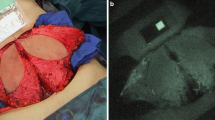

All 40 facial arteries from 20 patients were successfully imaged using 3D PC-MRA and CE-MRA. Of these, 15 arteries (37.5%) imaged using 3D PC-MRA (Fig. 2a) and 21 (52.5%) using CE-MRA (Fig. 2b) were exactly delineated by both radiologists. Because the enhancement of facial arteries is associated with contrast media (CM)-induced T1-shortening of the blood, it may be sometimes difficult to differentiate the small arteries from neighboring tissues due to CM contamination with CE-MRA compared with 3D PC-MRA (Fig. 3). For 1 of the 20 patients, the signals of facial arteries were lost with 3D PC-MRA but not with CE-MRA (Fig. 4).

To date, a limited number of articles have proposed the use of sonography, computed tomography, and MRI to evaluate the submandibular and submental LNs within VSLN flap [2, 20,21,22], but no study has explored the relationship between the submandibular glands and facial arteries during VSLN flap transfer. Pre-operative evaluation of LNs within VSLN flap and the courses of facial arteries prior to VSLN flap transfer is important, especially to determine the relationship while planning the ligation of branches to the submandibular glands and to reduce the surgical duration required to prepare facial arteries [23, 24]. The use of CM-enhanced CTA or MRA could facilitate the elucidation of the relationship between the submandibular glands and facial arteries prior to VSLN flap transfer. Although the cost and examination time of CTA are lower than those of MRA, the latter is more favorable owing to the lack of radiation exposure [25] and no risk of CM-induced nephropathy [26,27,28].

With a proper setting of acquisition timing following the administration of intravenous CM injection, CE-MRA is considered a promising method for the visualization of facial arteries [2, 8,9,10,11]. However, two factors should be considered when applying CE-MRA: complication of the delineation of facial arteries due to CM contamination of neighboring tissues (Fig. 3b) and potential risk of nephrogenic systemic fibrosis following the administration of gadolinium-based CM in patients with renal insufficiency [27, 29, 30]. Non-CE-MRA is a viable alternative method for the visualization of the main arteries in the neck region. 3D PC-MRA based on blood flow velocity has minimal background tissue intensity and demonstrates comparable results to CE-MRA in terms of the visualization of facial arteries (Figs. 2 and 3). In this study, there was no significant difference between CE-MRA and 3D PC-MRA in terms of the diagnostic abilities of facial arteries. The signal loss of facial arteries with 3D PC-MRA in one patient (Fig. 4) may be attributable to flow change, suggesting that an improper velocity encoding (VENC) value was used. An automatic method for rapid determination of a suitable range of the VENC values of specific vessels would be helpful when applying 3D PC-MRA to avoid blood flow perturbations.